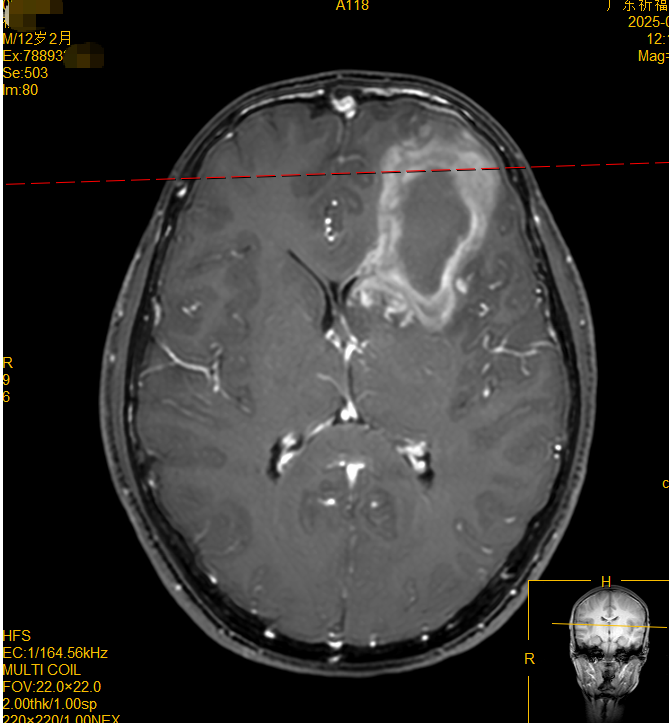

爸妈立即将他送到当地医院,检查结果让大家心头一紧——头部CT显示小越左侧额叶脑出血,进一步颅脑CTA检查显示左侧额叶动静脉畸形。医生建议尽快手术,但由于畸形血管团位置险要,周边密布重要神经,传统开颅手术极易引发大出血、神经功能损伤、癫痫等并发症。经过痛苦权衡,小越爸妈含泪拒绝了开颅手术方案,想寻找更安全的治疗方法。当地医院推荐小越转至广东祈福医院放疗中心接受射波刀治疗——一种无需开刀即可治疗脑部疾病的放射外科治疗技术。

120急救车把小越送到广东祈福医院时,他虽清醒但无法行走,根据检查结果,放疗中心主任刘秋华教授、谢荣辉医生等为小越制定了一套SBRT射波刀治疗方案。不需开刀,不需麻醉,治疗时小越全程清醒躺卧,每次20分钟左右,射波刀通过精准射线照射病灶而不伤及周边组织。3次照射配合药物治疗,小越上肢无力症状逐渐缓解,出院时已能自行下床行走。如今小越回院复查,一家人十分欣喜:瘤床已缩小,畸形血管大部分闭合,没有新的出血灶产生。小越已顺利重返校园,重新拥抱他应有的少年时光。

脑出血本是中老年患者多见的急症,怎么会发生在12岁小学生身上?原来,小越原本存在先天性的左侧额叶动静脉畸形,而熬夜打游戏则成了导火索——长时间的大脑刺激使他的交感神经持续紧张、血压不断升高,最终诱发悲剧。针对位置刁钻、无法手术的动静脉畸形(AVM),射波刀凭借其亚毫米级的超高精度,能在影像实时引导下,将高剂量射线精准聚焦于病灶,同时灵敏地避开周围的敏感功能区与正常脑组织,从而在不开刀、无痛的前提下实现治疗,并保护神经功能。